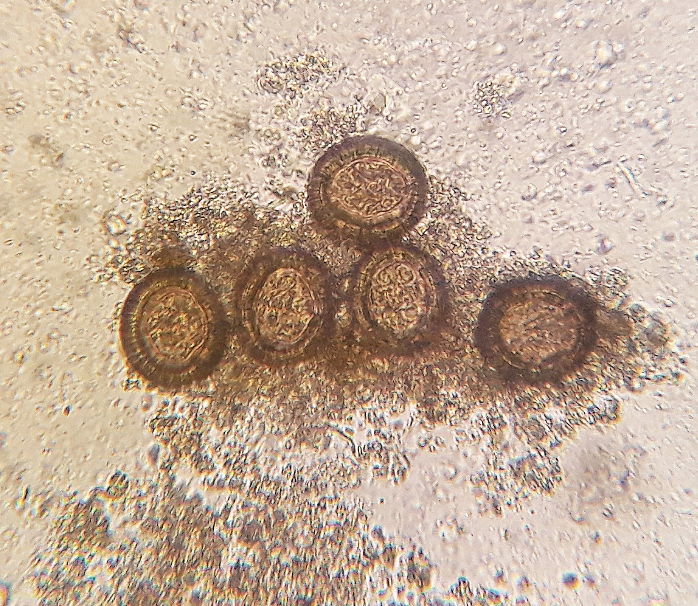

Eier des Bandwurmes